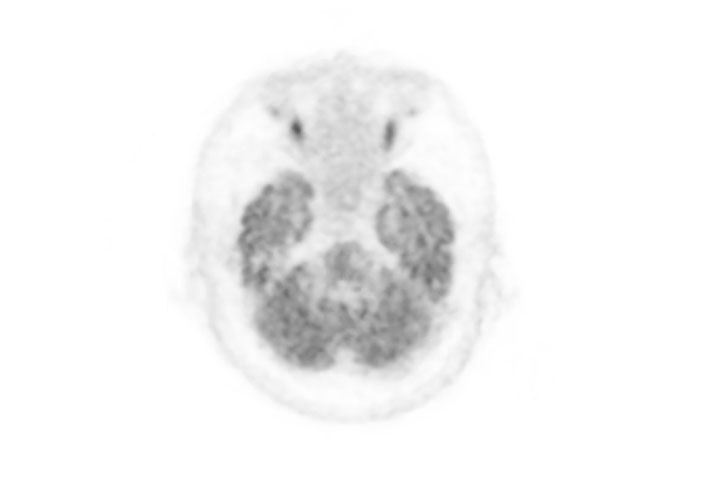

Head / Case2 : FDG

Courtesy : Kindai University Hospital

- Imaging protocol

- Injected dose: 3.29 MBq/kg, 18F-FDG

- Uptake time: 38 minutes

- Scan time: 30 minutes